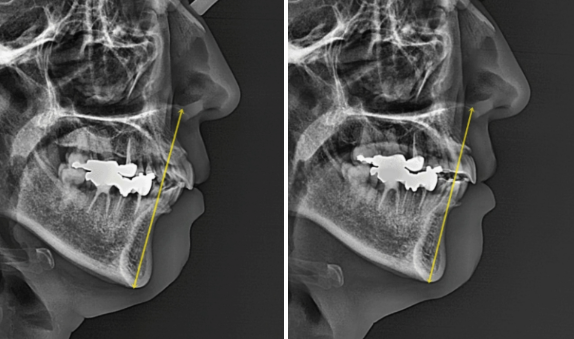

If you look at the superimposed X-rays before and after treatment, the effect of the retreatment is more clearly visible.

A fairly significant amount of self-rotation of the mandible occurred due to the intrusion and posterior movement of the entire dentition. Although treatment generally aims for about 2 mm, around 3 mm occurred.

The area that appeared to be chin retrusion improved, and the orange-peel chin relaxed, making the line from the lower lip to the chin look more natural.

When self-rotation occurs, the chin tip moves upward, and the vertical length of the lower face looks shorter from the front, making it appear smaller.

Also, due to self-rotation, the chin tip moves forward slightly.

So for chin retrusion with a small lower jaw, intrusion orthodontics is strongly recommended because it also helps resolve the retrusion.